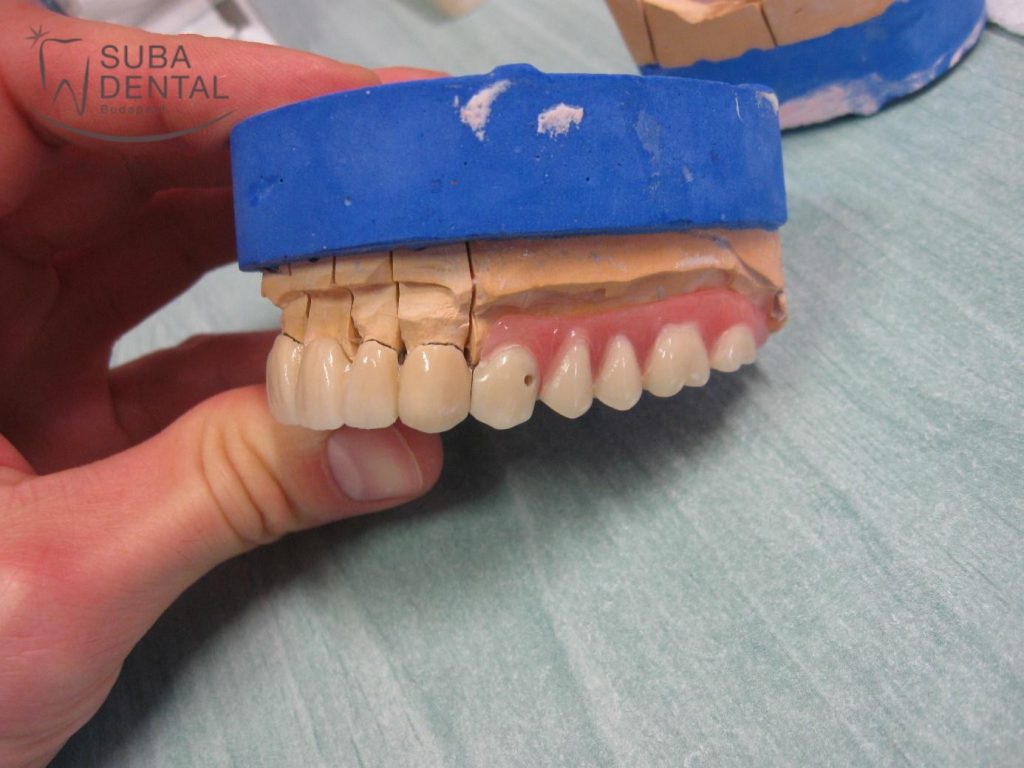

Alsó fémkerámia koronák saját fogakra és ragasztható implantátum koronák gipszmintán

Felső kombinált munka gipszmintán. Jól láthatóak a front koronák, melyhez kapcsolódik a kivehető fogsor rész egy speciális rejtett elhorgonyzással (MK1)

Felső fémkerámia körhíd gipszmintán